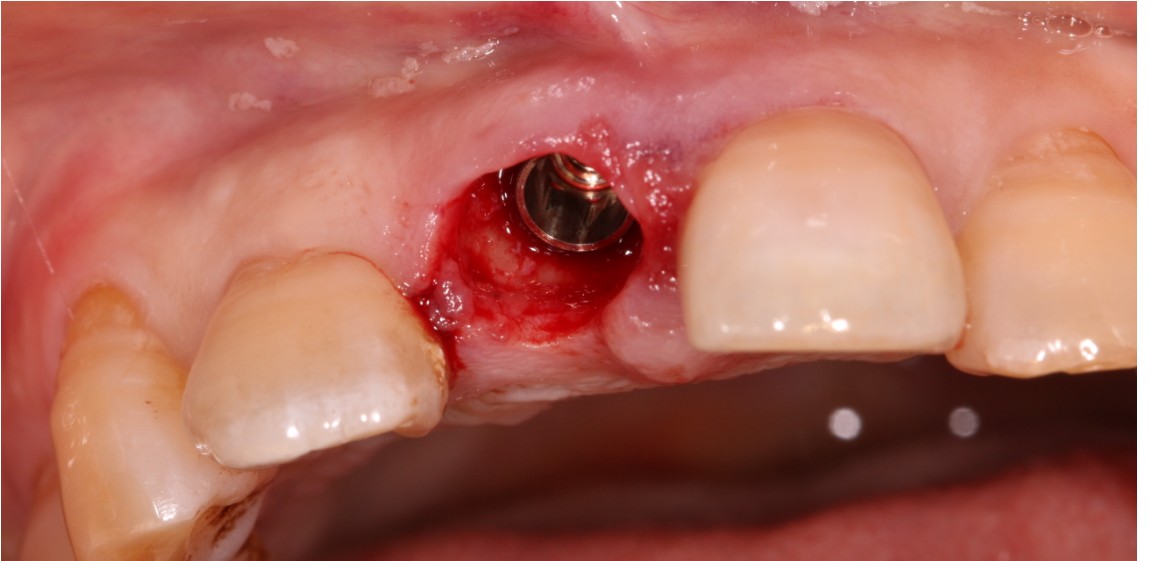

患者右上中切牙外伤导致冠根折,腭侧折面至骨下2mm,需要拔除患牙,x片显示唇腭侧牙槽骨完整,唇侧牙槽骨厚度1.5mm,根尖区剩余牙槽骨也有8mm,符合即拔即种即修复基本条件,患者知情同意下,术前两小时CEREC数字化扫描,设计种植导板,术前准备,拔除患牙,种植导板精密就位,种植窝完成制备,植入植体,拔牙窝间隙中植入Bio-oss骨粉,放置扫描杆,CEREC数字化扫描,一小时后即有一颗和左侧中切牙形态,颜色一致的右侧中切牙,不需要缝合,术后无疼痛,患者非常满意,CEREC数字化技术带给你无限可能!